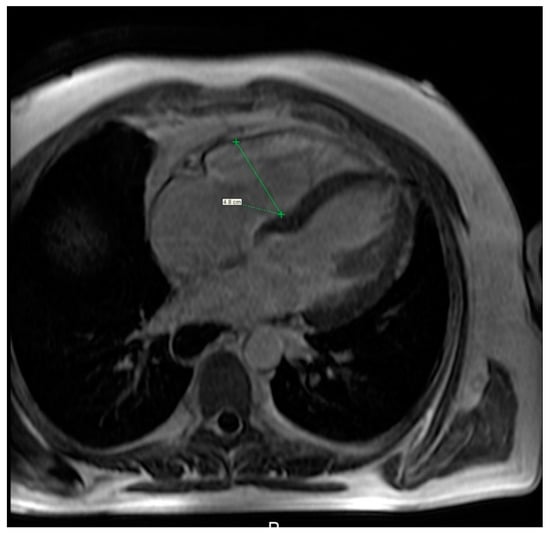

5.3. Heart

MRI is a useful modality of evaluation the morphology of the heart as well as function and vitality of the cardiac muscle, specifically the right heart (Figure 7, Video S2) [83], although comparison of MRI and the right heart catheterisation in assessment of PE was inconclusive. Bulging of the interventricular sept to the left correlates with the values of the pulmonary arterial pressure mostly in case of patients with advanced cases of PAH. Several studies have shown a delayed contrast enhancement of the right ventricle wall was seen in PAH patients (65–100%) [84,85]. While secondary to PAH right heart failure is the most severe cardiac complication in SSc patients, primary involvement of the heart is seen in a relatively large percent of patients—up to 15–35%. Cardiac fibrosis is the most common manifestation of primary heart involvement in scleroderma and might be seen in up to two-thirds of patients. Unlike other diagnostic imaging methods, MRI allows not only to visualise indirect symptoms of fibrosis (such as impaired ventricular filling and its enlargement) but also to directly asses the muscular involvement, eg. A delayed enhancement of the basal and central part of the left ventricle. Aside from fibrosis, some patients demonstrate also presence of myositis, which is seen as areas of increased signal intensity in T2-weighted images. Inflammation of the heart muscle is often seen in patients with symptoms of skeletal myositis [86,87].

Figure 7.

Cardiac magnetic resonance imaging of a 36-year-old woman with systemic sclerosis shows right ventricle dilation.